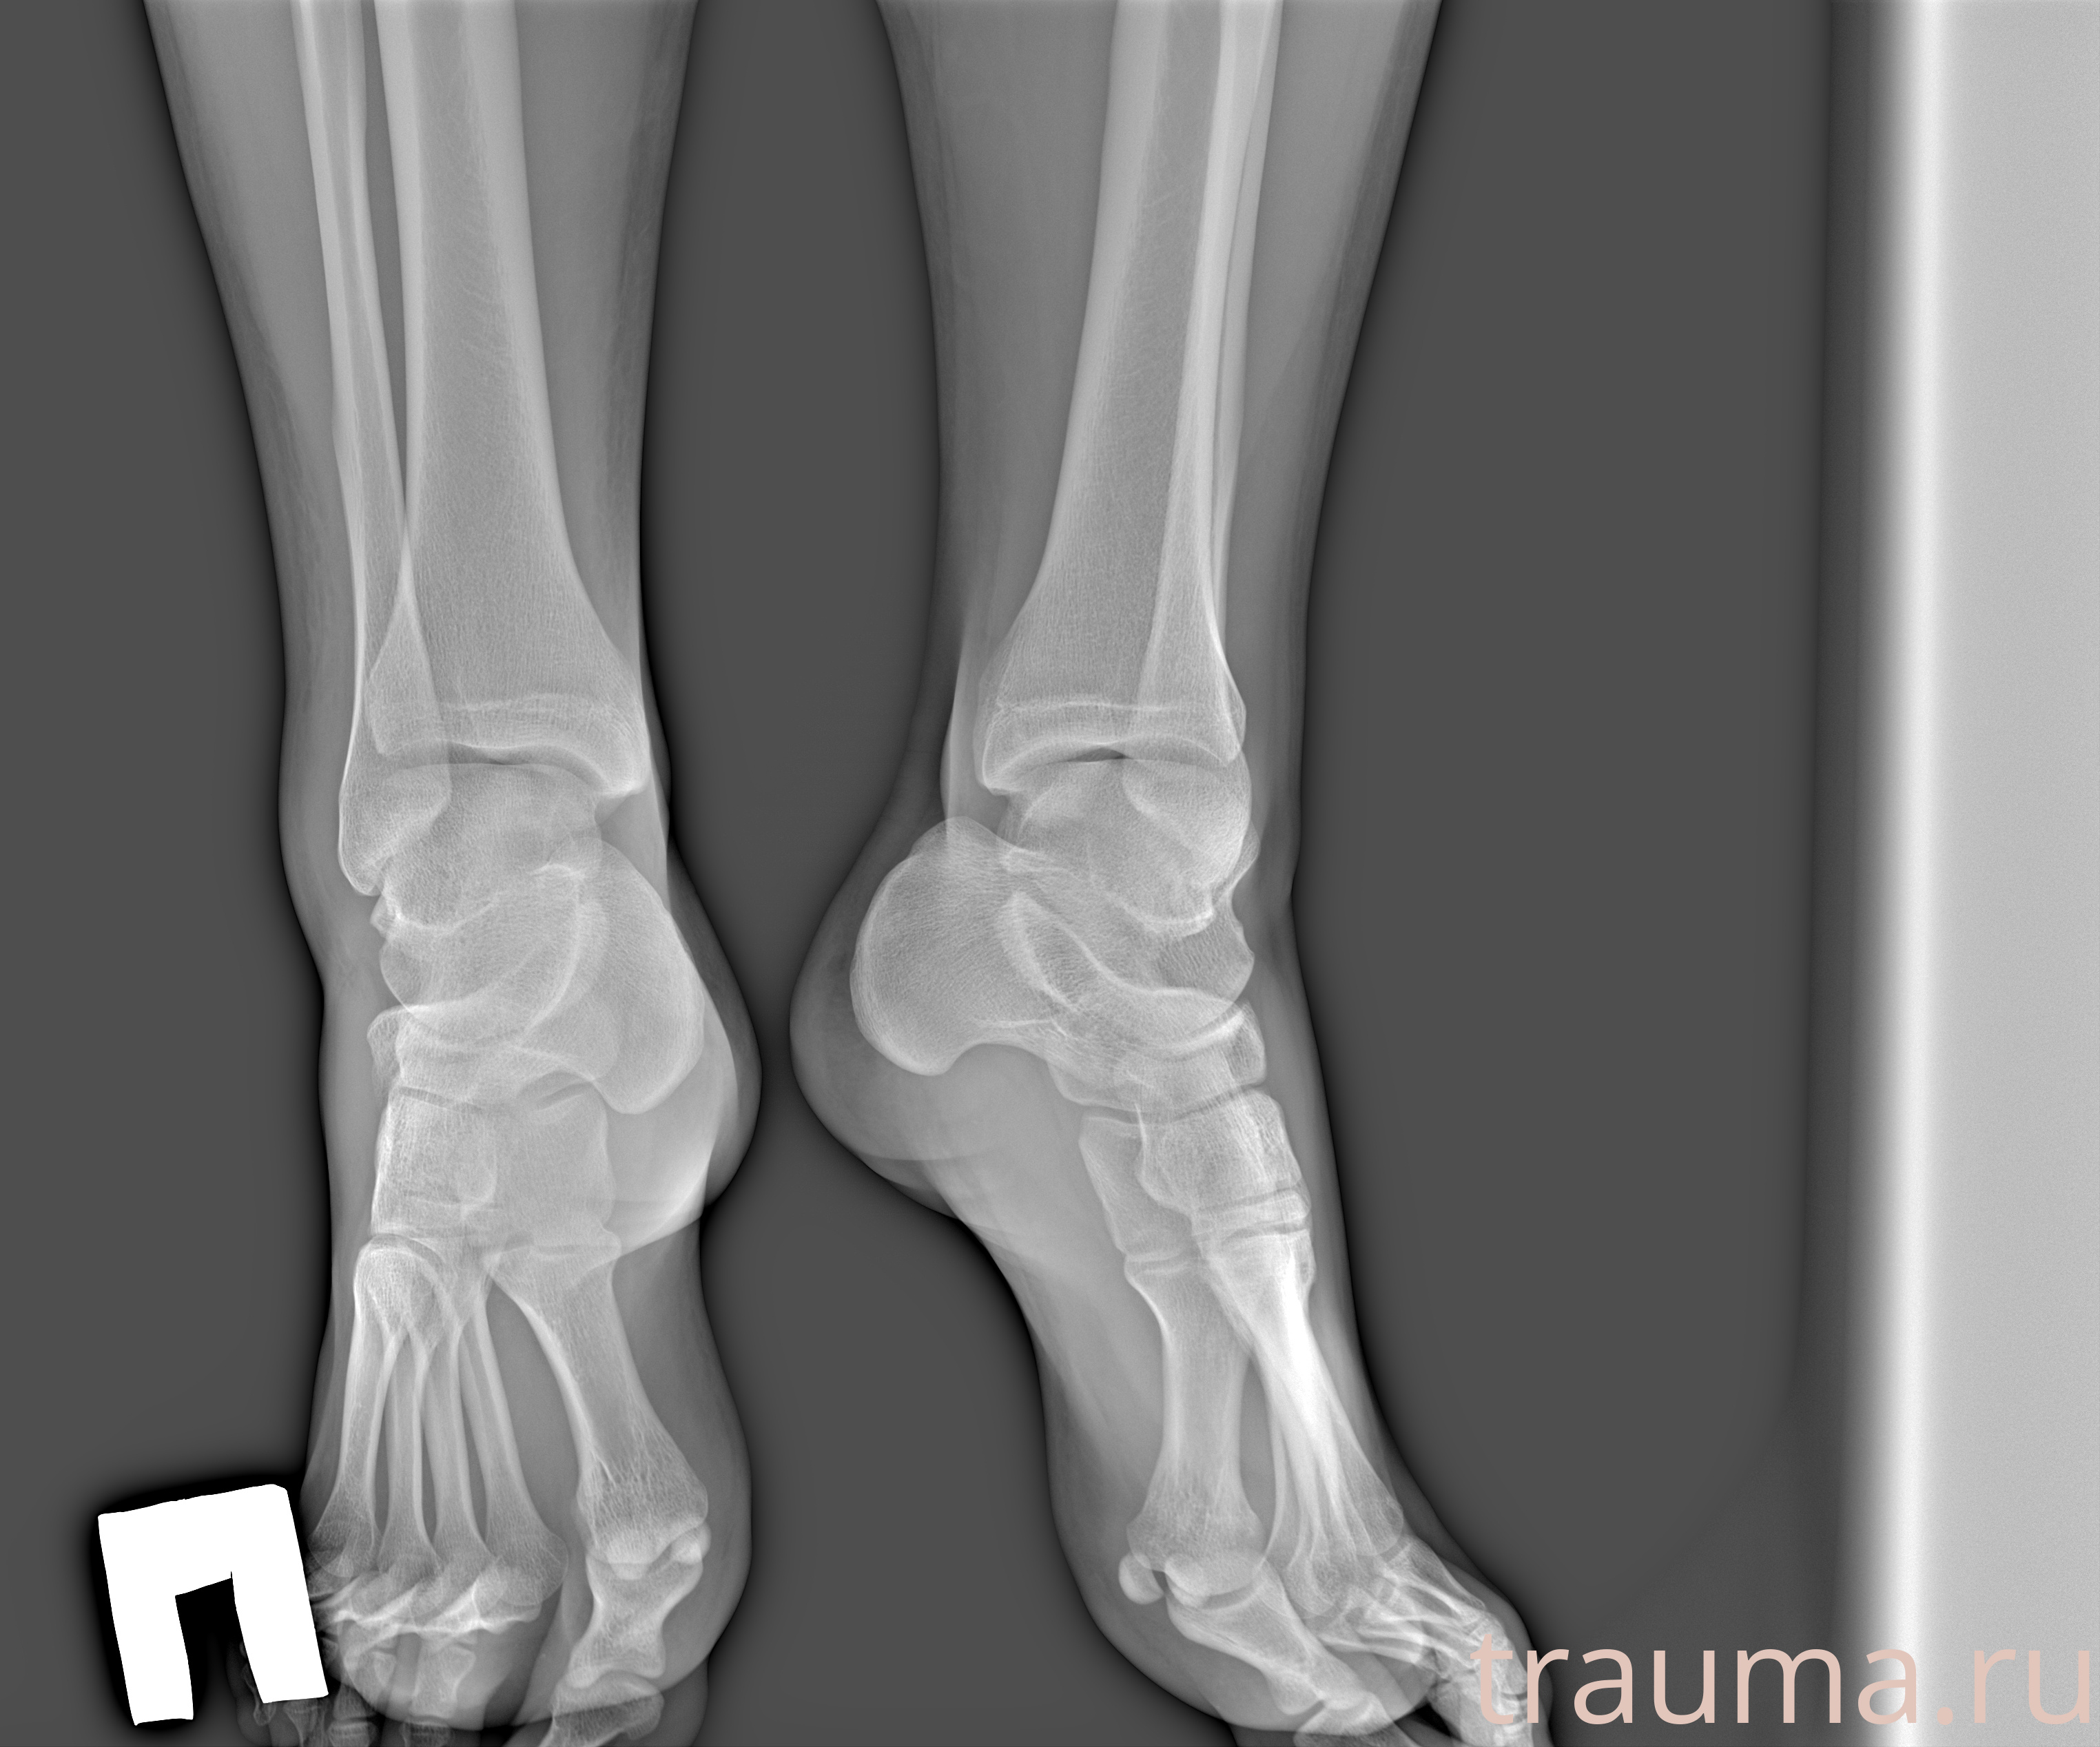

Рентгенограммы

Рентген на дому: по вашему адресу приезжает врач-рентгенолог, травматолог-ортопед с мобильным рентгеновским аппаратом, проводит диагностику травмы или заболевания, делает необходимые рентгенограммы, дает рекомендации по дальнейшему лечению. Получить качественные снимки в домашних условиях возможно благодаря уникальной методике, разработанной МосРентген Центром для института  Склифосовского